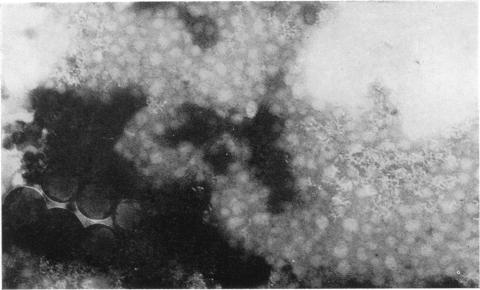

Electron microscopy of neurotropic African horse-sickness virus.

https://cdn.ncbi.nlm.nih.gov/pmc/blobs/d929/2134552/a994e2166929/jhyg00119-0153-a.jpg